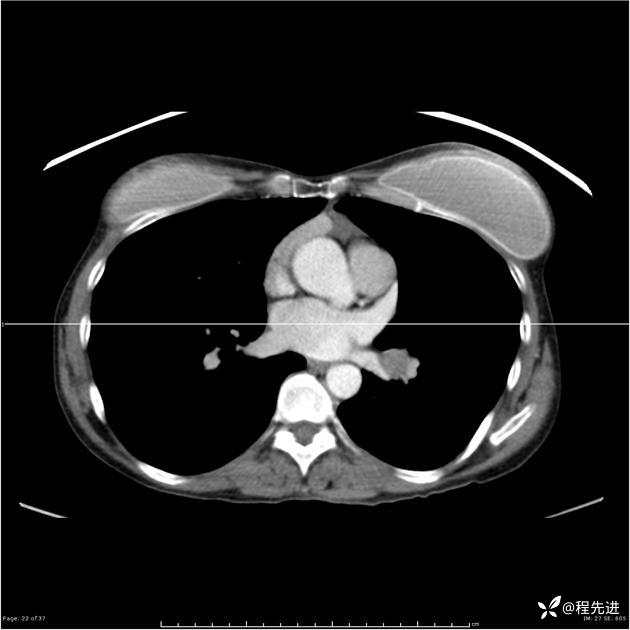

病例女,53岁,气管、左主支气管、下叶支气管内结节,乳头状瘤?期待你的精彩解读

女,53岁

乳头状瘤?